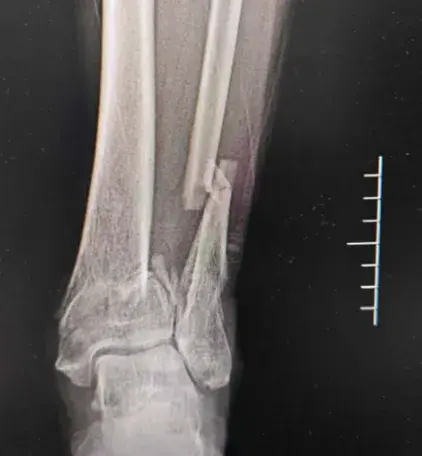

接到鉴定委托后,鉴定专家立即对李某的伤情进行了全面检查,并调取了相关的影像学资料。从检查结果来看,李某的骨折部位确实存在软组织肿胀,影像学显示的骨折形态也符合新鲜骨折的特征,再加上李某一口咬定自己近期只受过这一次伤,乍一看,所有证据都指向此次冲突是导致骨折的直接原因。

但多年的鉴定经验告诉专家,事情并没有这么简单。细心的专家发现,李某的骨折部位虽然有新鲜损伤的迹象,但结合影像学检查的细节来看,骨折的愈合状态与“近期刚受伤”的表述存在细微偏差——即便间隔仅1个月,两次同一部位受伤的影像学改变,也并非完全无法区分,只是这种细微差异,若非专业人士刻意留意,很容易被忽略。

看着专家坚定的眼神,李某知道自己再也瞒不住了,心理防线彻底崩塌,主动承认自己的骨折并非此次冲突所致,而是1个月前在老家意外受伤造成的。为了证明自己的说法,他还主动拿出了在老家医院就诊的病历资料,上面清晰地记录着当时的骨折诊断情况。“我以为间隔时间短,你们查不出来,没想到你们鉴定专家这么厉害,一点破绽都逃不过你们的眼睛!”李某满脸愧疚地说道,至此,这场刻意隐瞒的“伤情骗局”被彻底戳破。